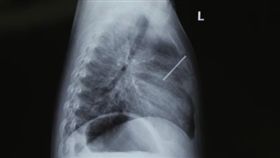

2歲娃拿釘槍自轟 鋼釘穿肺險中心臟

釘槍殺傷力極強,威力大的甚至能射穿1公分的鋼板,但沒...